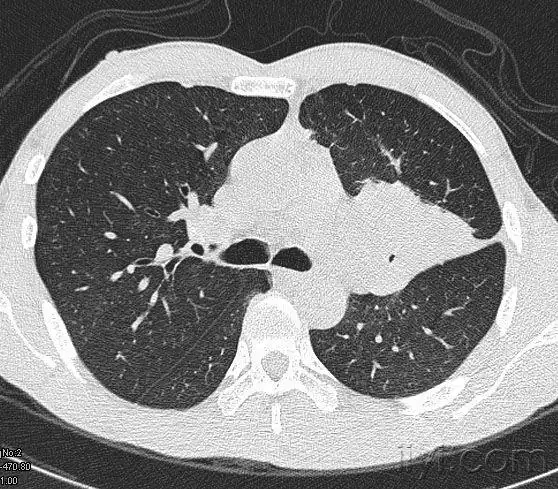

中央型肺癌ct

简述中央型肺癌特点及影像表现

在ct上,肺癌按照发生部位可以分为以下3种类型: 1,中央型肺癌:指肿瘤